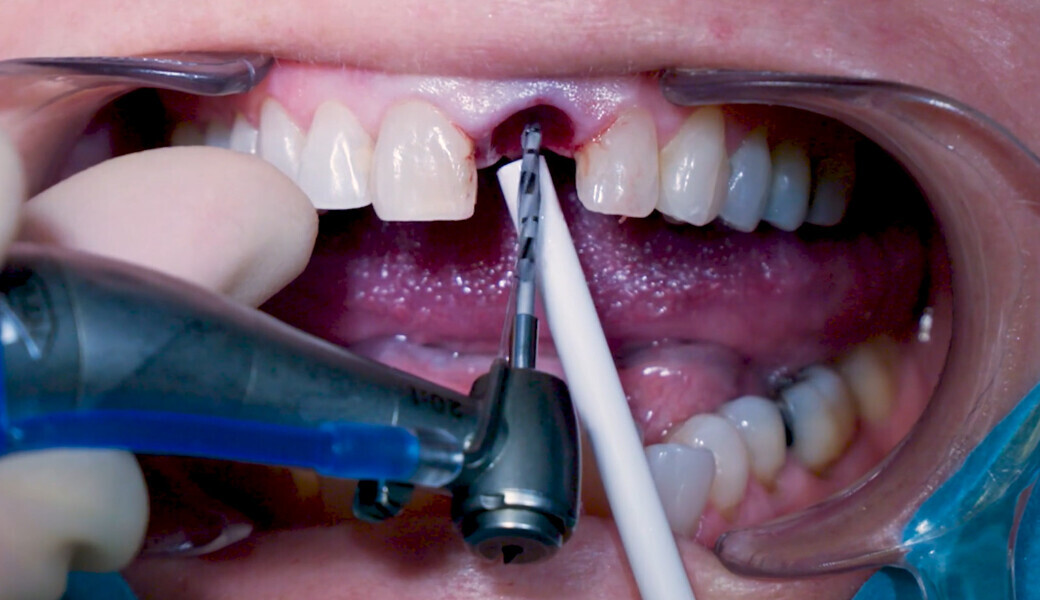

Fig. 8: Osteotomy with Ø 3.2 mm drill.